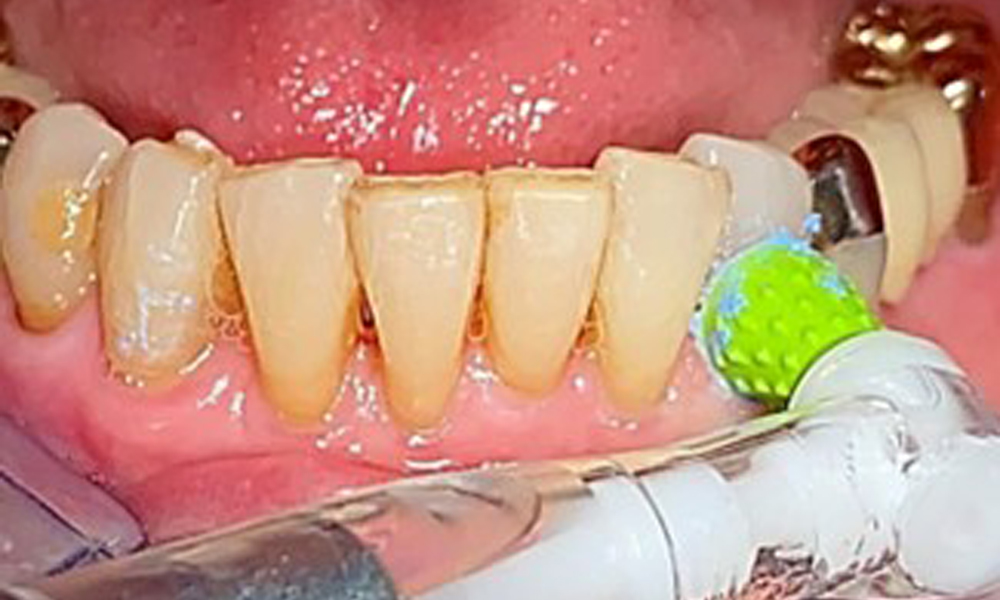

The patient was fitted with a combined removable maxillary telescopic prosthesis more than 25 years ago (Fig. 1, Fig. 2, Fig. 3) and is very happy with her dentures. The patient has an adequate fixed denture for the mandible (Fig. 4).

The dental findings are as follows: Combined removable implant and tooth-supported telescopic prostheses on implants 15, 13, 21, 23, 24, 25 and tooth 11 (Fig. 1, Fig. 2, Fig. 3). The patient was fitted with a fixed mandibular denture. Adequate bridges were present over 37 to 34 and 45 to 47 (Fig. 4), the crown margins were intact and there were no active caries. A composite filling with a marginal gap was present on tooth 43. There was mandibular gingival recession, exposing 1 to 3 mm of root surface. This also applies to 11.